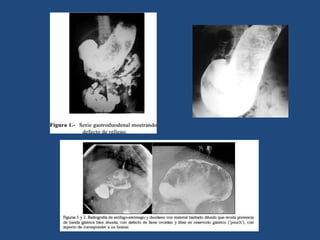

El documento habla sobre los bezoares, que son masas compactas que se forman en el intestino por la acumulación de residuos no digeribles. Los más comunes son los fitobezoares de origen vegetal y los tricobezoares formados por la ingestión de cabellos humanos. Los fitobezoares generalmente se forman debido a problemas para masticar o digerir los alimentos, mientras que los tricobezoares se asocian con trastornos psiquiátricos y la ingestión compulsiva de cabellos. El diagnóstico se realiza mediante